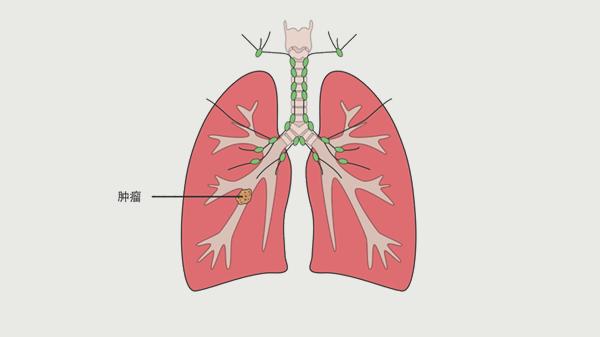

导致肺癌的“祸根”,离不开这4个因素,第一个是最常见的

肺癌发病率逐年攀升,已经成为威胁现代人健康的重要疾病。很多人以为只有吸烟才会导致肺癌,其实诱发因素远不止于此。今天我们就来聊聊那些容易被忽视的肺癌风险因素,特别是第一个因素,几乎每个人都可能接触到。